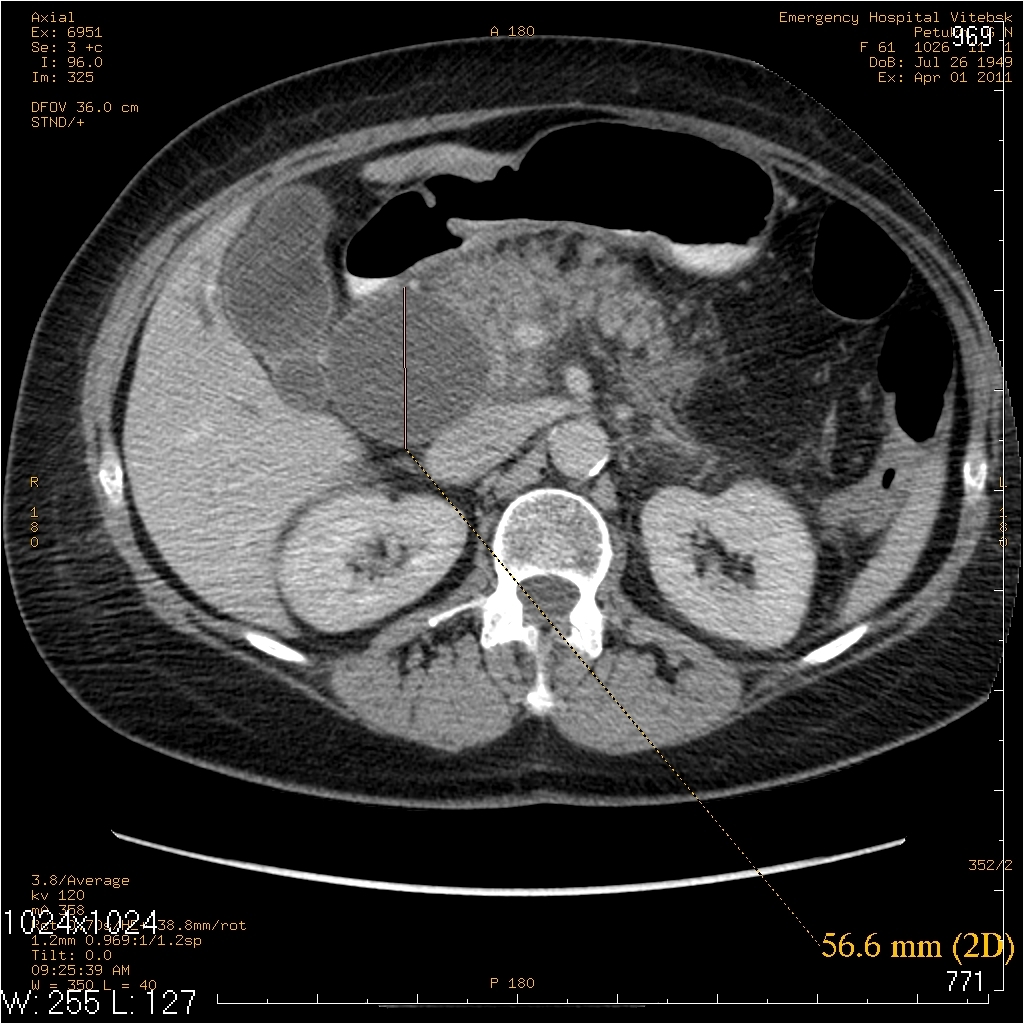

жалобы на периодические боли в правом подреберье, желтушность кожных покровов. считает себя больной в течении 2лет, когда впервые появились боли в правом подреберье. госпитализирована 25.03., 31.03. произведено МСКТ, реконструктивная операция 31.03.

На МСКТ: Киста холедоха (грушевидной формы ~95х50мм). ЖКБ: холецистит, холедохолитиаз (в области БДС дефект наполнения просвета 12пк, расширение вирсунгова протока до 10мм). Билиарная гипертензия. Отёчный панкреатит, парапанкреатит.

На операции: Киста холедоха (терминальный отдел холедоха 2мм). ЖКБ: хр.холецистит, холедохолитиаз (конкременты до 4мм). Стеноз папилы 3ст. (блокада вирсунгова протока, общий желчный и панкреатический протоки впадают в двенадцатиперстную кишку по отдельности). Острый панкреатит, парапанкреатит.